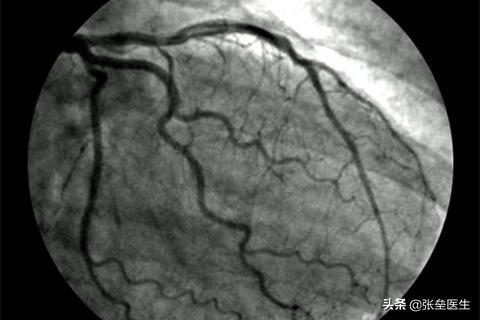

③心肌缺血时:这点其实就和围绕心脏表面的供血血管(冠状动脉)有关,最为常见就是动脉粥样硬化,血管出现狭窄,那心肌供血不足就会有胸痛的表现,如果活动后疼痛会发作或者加剧,随着血管狭窄程度进一步严重,可能休息的时候都会有心绞痛发作,如果再继续发展下去,血管闭塞,即出现心肌梗死,这时候就会有心前区压榨性的疼痛。

⑤导管及心血管造影检查:用于其它诊断手段难以确诊的心脏疾病。目前冠状动脉造影是诊断冠状动脉粥样硬化性心脏病的“金标准”,可以明确冠状动脉有没有狭窄、狭窄的部位、程度、范围,并为治疗方法提供依据,同时可以进行左心室造影,对心功能进行评估。